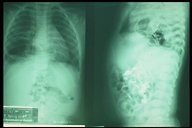

Plain X-ray (right ) and contrast study (left) in a child with right-sided diaphragmatic hernia with sac, the contrast outlined the bowel in the right thoracic cavity